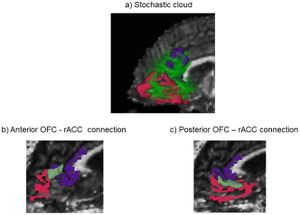

- 4.20 Orbitofrontal Cortex Volume in Area 11/13 Predicts Reward Devaluation, but not Reversal Learning Performance, in Young and Aged Monkeys